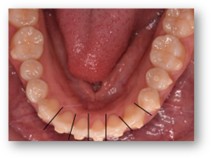

(初診時) (ワイヤー除去前) (ワイヤー除去後)

※この方はワイヤー矯正後、マウスピース矯正に移行しています